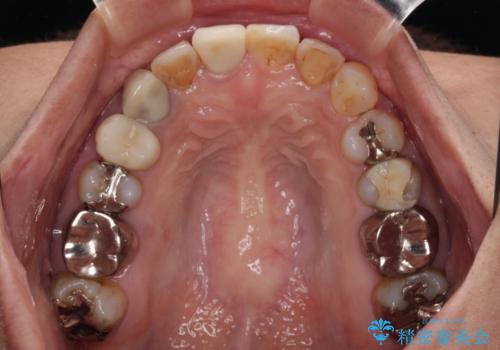

- 上下前歯のデコボコを気にして来院された患者様です。

歯列としては、ワイヤー装置でもインビザラインでも、どちらでも対応可能でしたが、処置されている歯が多く、ワイヤー装置を装着するためには処置歯のやり直しが必要な状態でした。

インビザラインでもアタッチメントを装着できないという同様のデメリットがありますが、比較的矯正治療を行いやすい歯列であったので、インビザラインによる矯正治療を行うこととしました。

術中や仕上がりに特に大きなトラブルはなく、スムーズに治療を終えることができました。